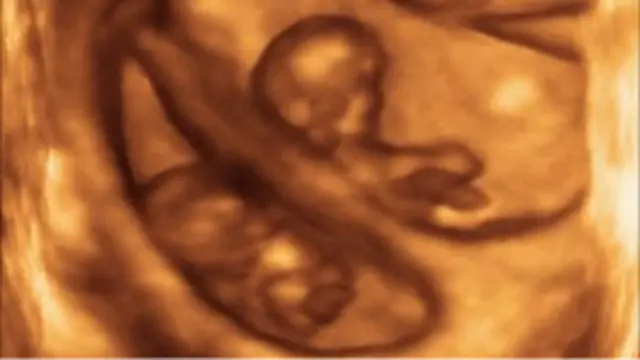

Mpango wa uzazi ujulikanao kama IVF ama uzazi wa kutegemea sindano umehusiashwa na kuzuka kwa uvimbe katika fuko la uzazi baadaye katika maisha ya mtumiaji.

Wanawake wanaopewa dawa ya kurutubisha mayai ya uzazi waligunduliwa kuwa na uwezkano mkubwa wa kupata uvimbe wa kizazi ambao unaweza kugeuka kua saratani, wanasema wataalamu wa Uholanzi.